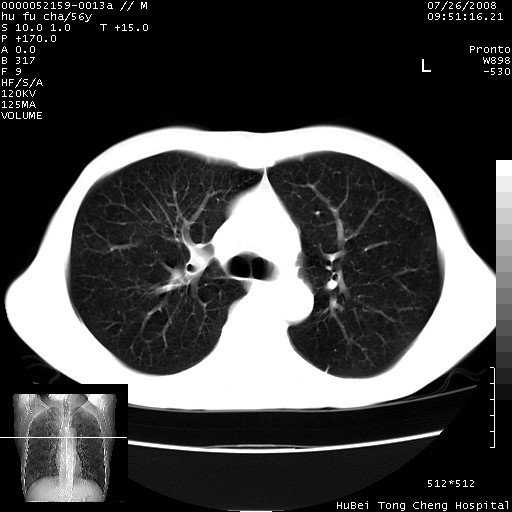

以下是引用zsl6918在2008-8-25 22:47:00的发言:[br]胸骨,胸椎及肋骨均可见多发转移表现,肝内低密度结节不除外转移。原发灶可能在右肺。双侧可见支扩表现。

以下是引用卜一在2008-8-26 8:02:00的发言:[br][br] 支持:肺癌并肺内,胸骨,胁骨,胸椎及肝内转移!另:左肺支气管扩张征伴感染! [br]

以下是引用zjzjr在2008-8-26 11:03:00的发言:[br]支持:肺癌并肺内,胸骨,胁骨,胸椎及肝内转移!另:左肺支气管扩张征伴感染!